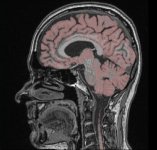

Ein besonders aktueller Schwerpunkt des Welfenlab ist die Visualisierung von Voxeldaten aus dem Bereich der Medizin. Unter einem Voxel kann man sich das dreidimensionale Gegenstück eines Pixels vorstellen. Während ein Pixel (bestehend aus einer x und y Koordinate zusammen mit einem Farbwert) einen Punkt auf einem Computermonitor beschreibt, besitzt ein Voxel zusätzlich eine z-Koordinate. Solche Voxeldaten werden u.a. durch verschiedene bildgebende Verfahren der Medizin gewonnen, z.B. durch Computertomographie (CT) oder Magnetresonanztomographie (MRT). Aus Sicht der Informatik stellt sich die Frage, wie solche Voxeldaten in einer für den Menschen verständlichen Art und Weise dargestellt werden können. Je nach Anwendung kommt es dabei entweder darauf an eine besonders schöne und leicht verständliche Visualisierung zu finden, oder eine möglichst schnelle, interaktive Darstellung bei der sich der Betrachter um das virtuelle Objekt herum oder sogar hindurch bewegen kann.